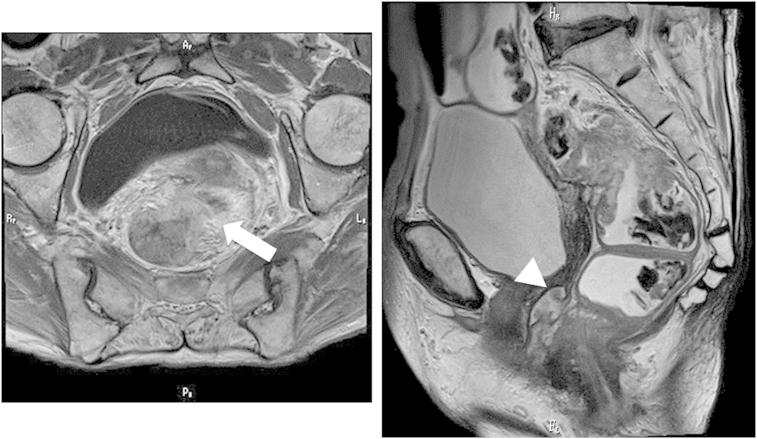

We present a case of isolated vaginal metastasis from rectal cancer in a 78-year-old female patient. The patient had no symptoms related to vaginal tumor. Magnetic resonance imaging (MRI) showed thickening of the middle rectum and a vaginal tumor. Biopsy from the vaginal tumor showed adenocarcinoma, similar to the rectal lesion. Low anterior resection with ileostomy, hystero-oophorectomy, and transvaginal tumor resection was performed. After nineteen months, computed tomography scan revealed multiple lung metastases and recurrent tumor in the pelvis. The patient refused chemotherapy and is alive three months after developing recurrent disease.

We should keep the vagina within the field of view of pelvic MRI, which is one of the preoperative diagnostic tools for colorectal cancer. If female patients show gynecological symptoms, gynecological examination should be recommended. Isolated vaginal metastases are an indication for surgical resection, and adjuvant chemotherapy is also recommended.

我们报告一例78岁女性患者的直肠癌孤立性阴道转移病例。患者无阴道肿瘤相关症状。磁共振成像(MRI)显示直肠中段增厚及阴道肿物。阴道肿物活检显示为腺癌,与直肠病变相似。行低位前切除术加回肠造口术、子宫卵巢切除术及经阴道肿瘤切除术。19个月后,计算机断层扫描显示多发肺转移及盆腔肿瘤复发。患者拒绝化疗,复发疾病后3个月仍存活。

我们应将阴道纳入盆腔MRI的视野范围,盆腔MRI是结直肠癌术前诊断工具之一。如果女性患者出现妇科症状,建议进行妇科检查。孤立性阴道转移是手术切除的指征,也建议辅助化疗。